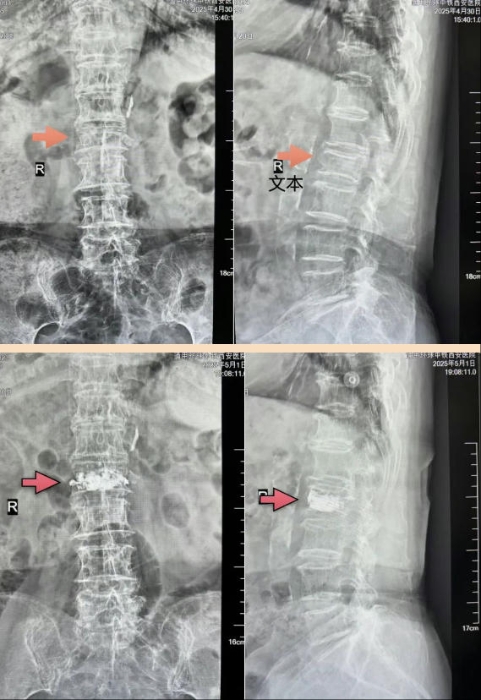

直擊“醫”線|九旬老人遇骨折,妙手救治續走健康路

當五一的歡笑聲漫過城市街巷,我院依然激蕩著最動人的“勞動號子”。勞動節前一天,92歲的申奶奶腰椎意外遭遇骨折,如此高齡,讓人不由得捏了一把汗。

申奶奶得知骨科姬傳磊主任技術高超,擅長微創骨科手術,遂在家人的陪伴下前來就診。因患者高齡,骨折帶來的痛苦不言而喻,申奶奶不能翻身和站立,臥床時間長還有可能肺部感染,同時患者有心臟病史,隨時有生命危險……

姬主任仔細評估后,決定為老人實施骨水泥微創手術。這種手術具有創口小、恢復快的特點,可讓申奶奶免于繁瑣的開放手術,減輕痛苦。

術前與心血管內科、麻醉科聯合制定多套應急預案,術中,醫生們謹慎而細致的操作,讓申奶奶感受到了專業醫療與人性關懷的結合。術后,老人疼痛明顯緩解,身體狀況也穩定下來。醫護人員細致入微的關懷,更讓這位老人備受溫暖。